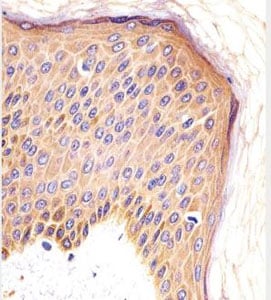

IHC (Immunohiostchemistry)

(AAA283572 staining CSF1R in human skin sections by Immunohistochemistry (IHC-P - paraformaldehyde-fixed, paraffin-embedded sections). Tissue was fixed with formaldehyde and blocked with 3% BSA for 0. 5 hour at roomtemperature; antigen retrieval was by heat mediation with a citrate buffer (pH6). Samples were incubated with primary antibody (1/25) for 1 hours at 37°C. A undiluted biotinylated goat polyvalent antibody was used as the secondary antibody)

IHC (Immunohistochemistry)

(AAA283572 staining CSF1R in human skin sections by Immunohistochemistry (IHC-P - paraformaldehyde-fixed, paraffin-embedded sections). Tissue was fixed with formaldehyde and blocked with 3% BSA for 0. 5 hour at roomtemperature; antigen retrieval was by heat mediation with a citrate buffer (pH6). Samples were incubated with primary antibody (1/25) for 1 hours at 37°C. A undiluted biotinylatedgoat polyvalent antibody was used as the secondary antibody.)